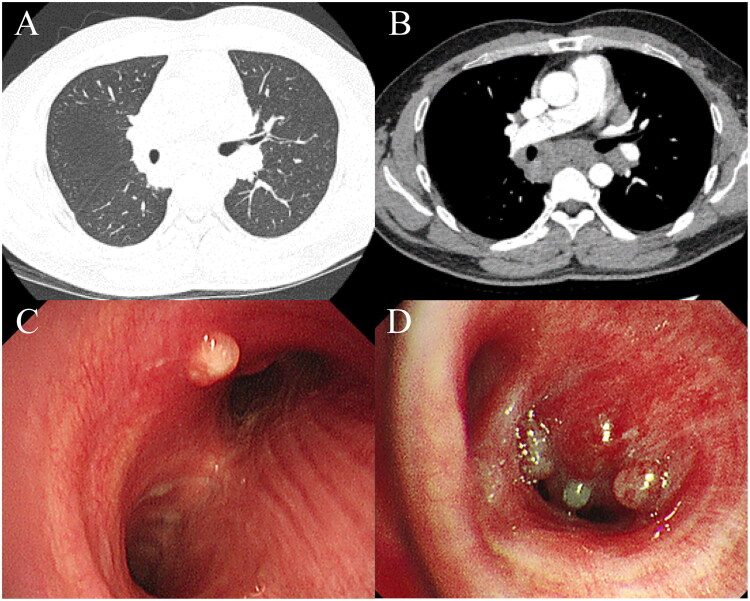

Results: The median age of onset for pulmonary sarcoidosis was 50 years, with females accounting for 68.94% of the patients. Common symptoms of pulmonary sarcoidosis included cough, sputum production, dyspnea, and chest pain, while approximately 34.12% of patients were asymptomatic. Fever, fatigue, and night sweats occurred less frequently in pulmonary sarcoidosis patients than in those with intrathoracic lymph node TB. Uveitis and myocardial sarcoidosis were observed exclusively in pulmonary sarcoidosis patients. The median time from symptom onset to the diagnosis of pulmonary sarcoidosis was up to three months. Approximately 47.29% of pulmonary sarcoidosis patients had reduced peripheral blood lymphocyte counts, and 94.12% exhibited symmetric enlargement of hilar lymph nodes on chest CT. Both pulmonary sarcoidosis and intrathoracic lymph node TB showed granulomatous inflammation, with 64.36% of intrathoracic lymph node TB cases presenting necrotic foci. Bronchoscopy was the primary method for biopsy, and only 11.06% of pulmonary sarcoidosis patients had multiple nodules in the tracheal or bronchial mucosa, with a low positivity rate for pathogen tests.

Conclusion: Pulmonary sarcoidosis predominantly affects middle-aged and young women and can be differentiated from intrathoracic lymph node TB by the presence of uveitis and myocardial sarcoidosis, although these manifestations are rare. A significant proportion of pulmonary sarcoidosis patients experience a reduction in their peripheral blood lymphocyte count. Chest CT scans often reveal symmetric bilateral enlargement of hilar lymph nodes, and in some cases, multiple nodules in the tracheal or bronchial mucosa. Both pulmonary sarcoidosis and intrathoracic lymph node TB show granulomatous inflammation, but tuberculosis lesions are more likely to necrose.